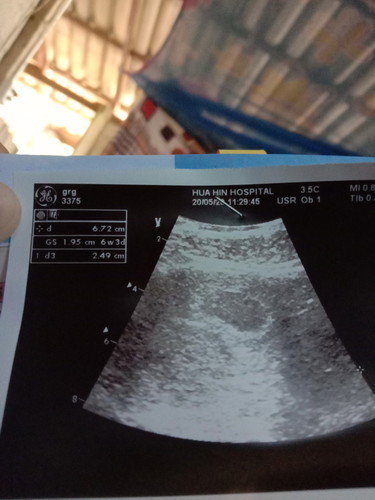

ตอนไป อัลตร้าซาวด์อายุครรภ์ได้ 6 week 3 วันแต่ตอนนี้ อายุครรภ์ 8 wจะ 9 weeks แล้ว คิดว่าเล็กเกินไปไหมคะตอนอัลตร้าซาวด์อยากรู้ว่าจะโตขึ้นอีกไหม ตอนนี้รู้สึกกังวลค่ะ